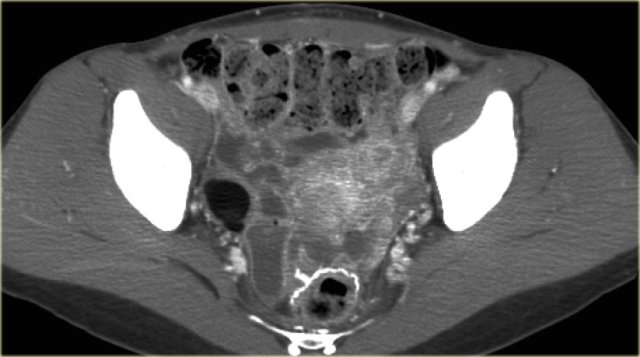

The next case is a transabdominal ultrasound that shows a left-sided multiloculated cystic mass.

This looks like a cystic ovarian neoplasm but no ovary could be identified.

CT of the same patient shows a multi-loculated cystic mass adjacent to the bladder, connected to the left ovarian vein (arrow).

There are thick septations and irregular wall thickening.

On the basis of this CT the distinction between a benign ovarian lesion such as as cystadenofibroma and a malignant ovarian lesion cannot be made.

The lesion was resected and found to be a cystadenofibroma.